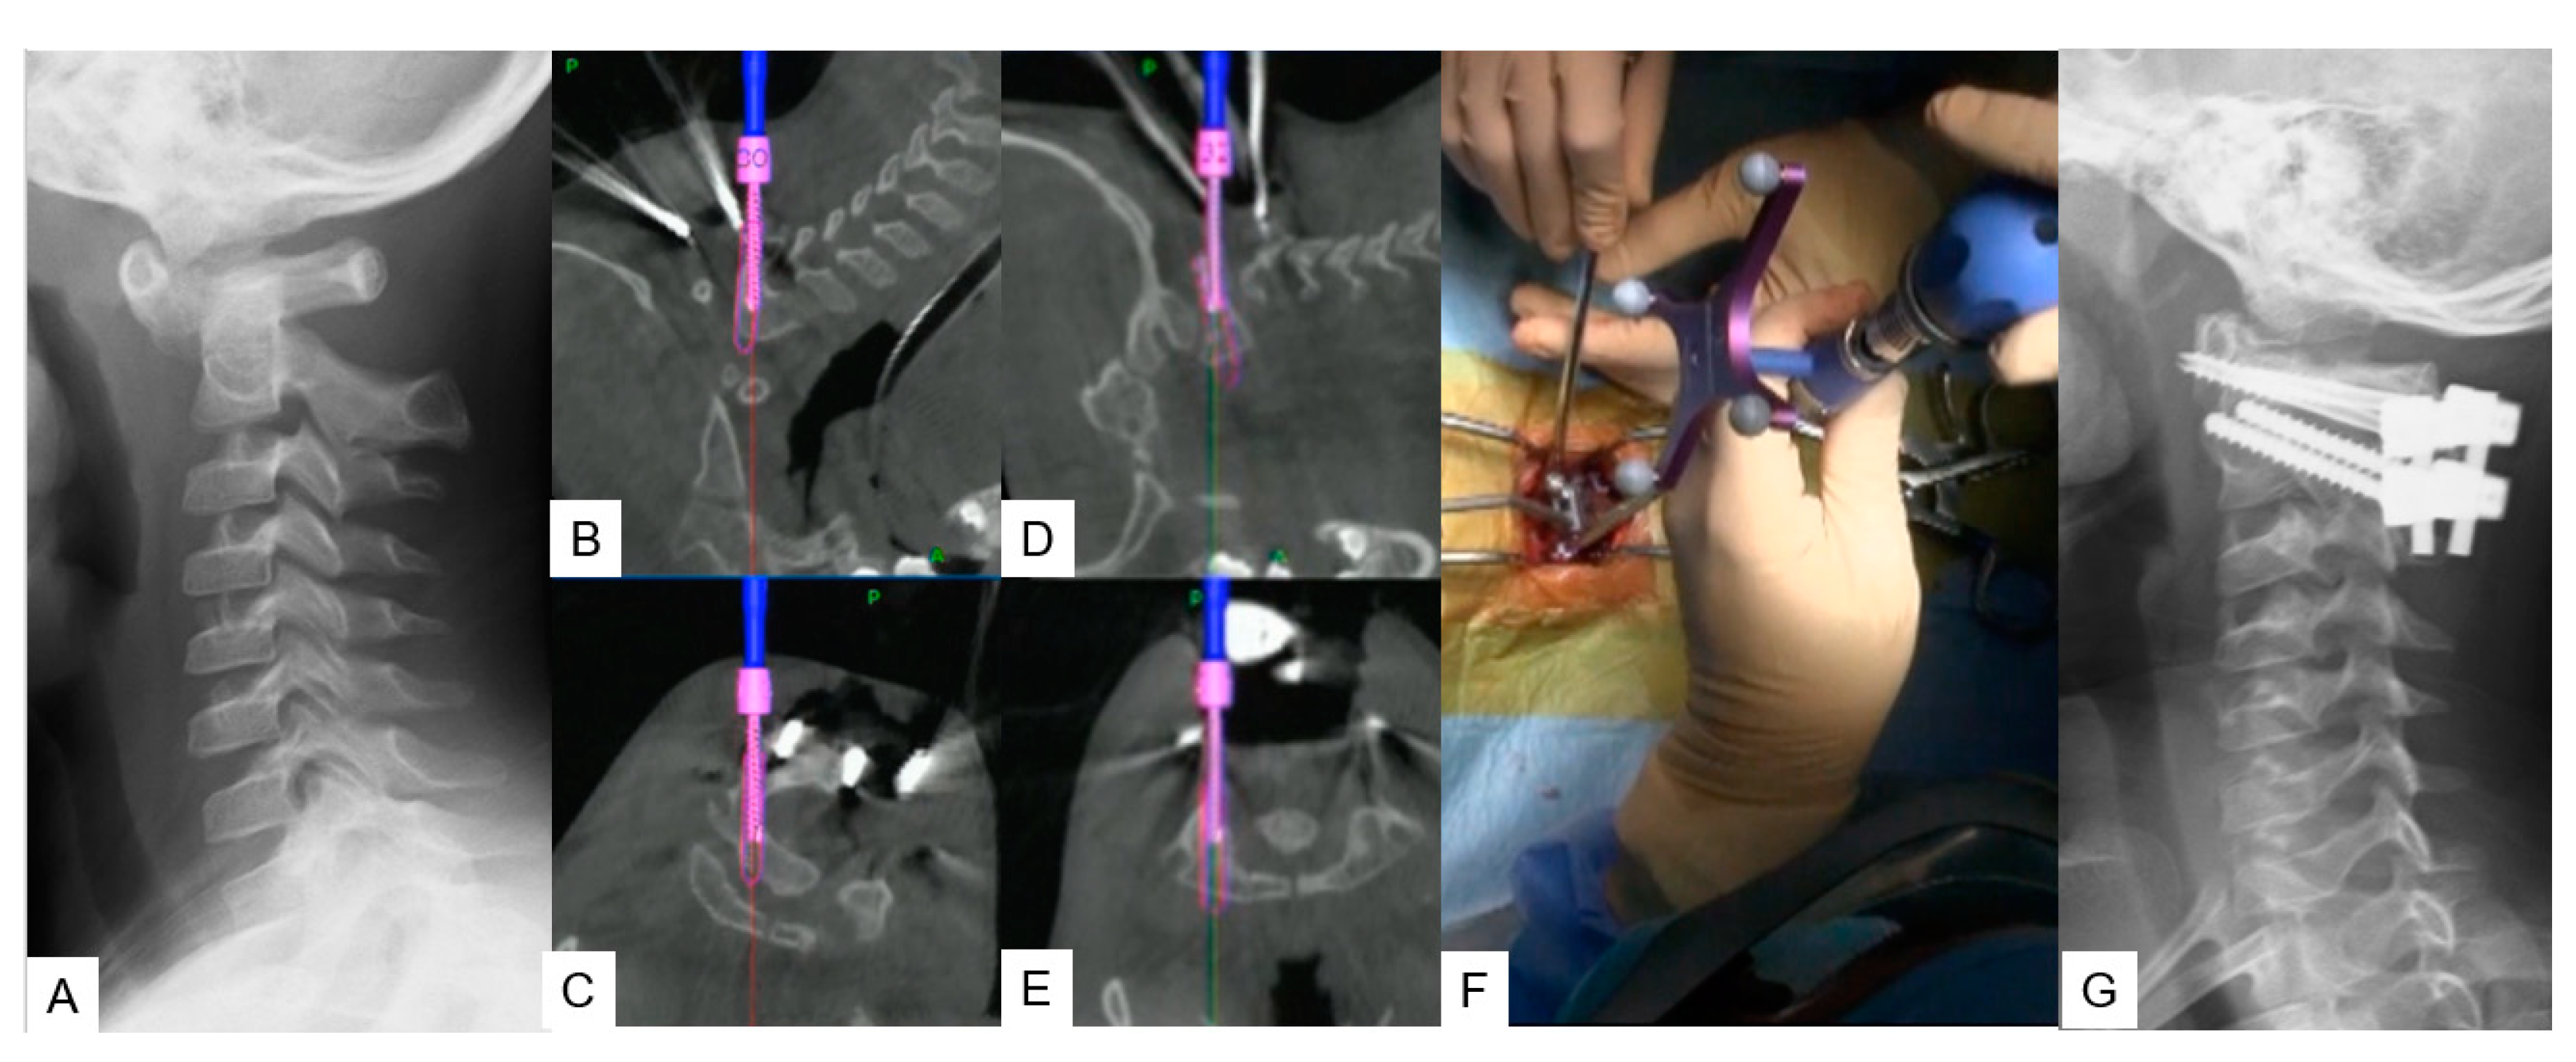

Figure 3. Case 3, 5 years old male, Down syndrome, Anterior atlantoaxial subluxation, Modified Goel technique. A: Preoperative lateral cervical radiogram, B, C: Intraoperative navigation image of C2 pedicle screw insertion, D, E: Intraoperative navigation image of C1 lateral mass screw insertion, F: Intraoperative image, F: Postoperative lateral cervical radiogram.

2.2.2. Modified Goel technique

Stabilization of C1-C2 level can prove to be challenging due to lower fusion rates compared to the other cervical levels, as the motion in this particular segment is significantly higher. For this approach we propose C1 LMS with C2 pedicle screw insertion. A careful posterior approach as described in Midpoint technique should be made to avoid vessel injury. After that the ideal entry point should be marked with a high speed burr without applying strong downward forces at C2 vertebra. Finally, the trajectory is made by using a navigated pedicle probe with appropriate tapping.